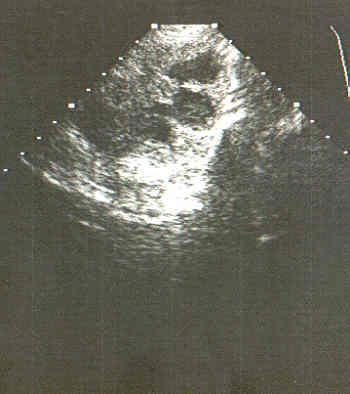

Vorsteherdrüse, Ultraschall

Mittels Ultraschall können Veränderungen in der Prostata - wie hier im Bild gefährliche Zysten -sicher erkannt werden.